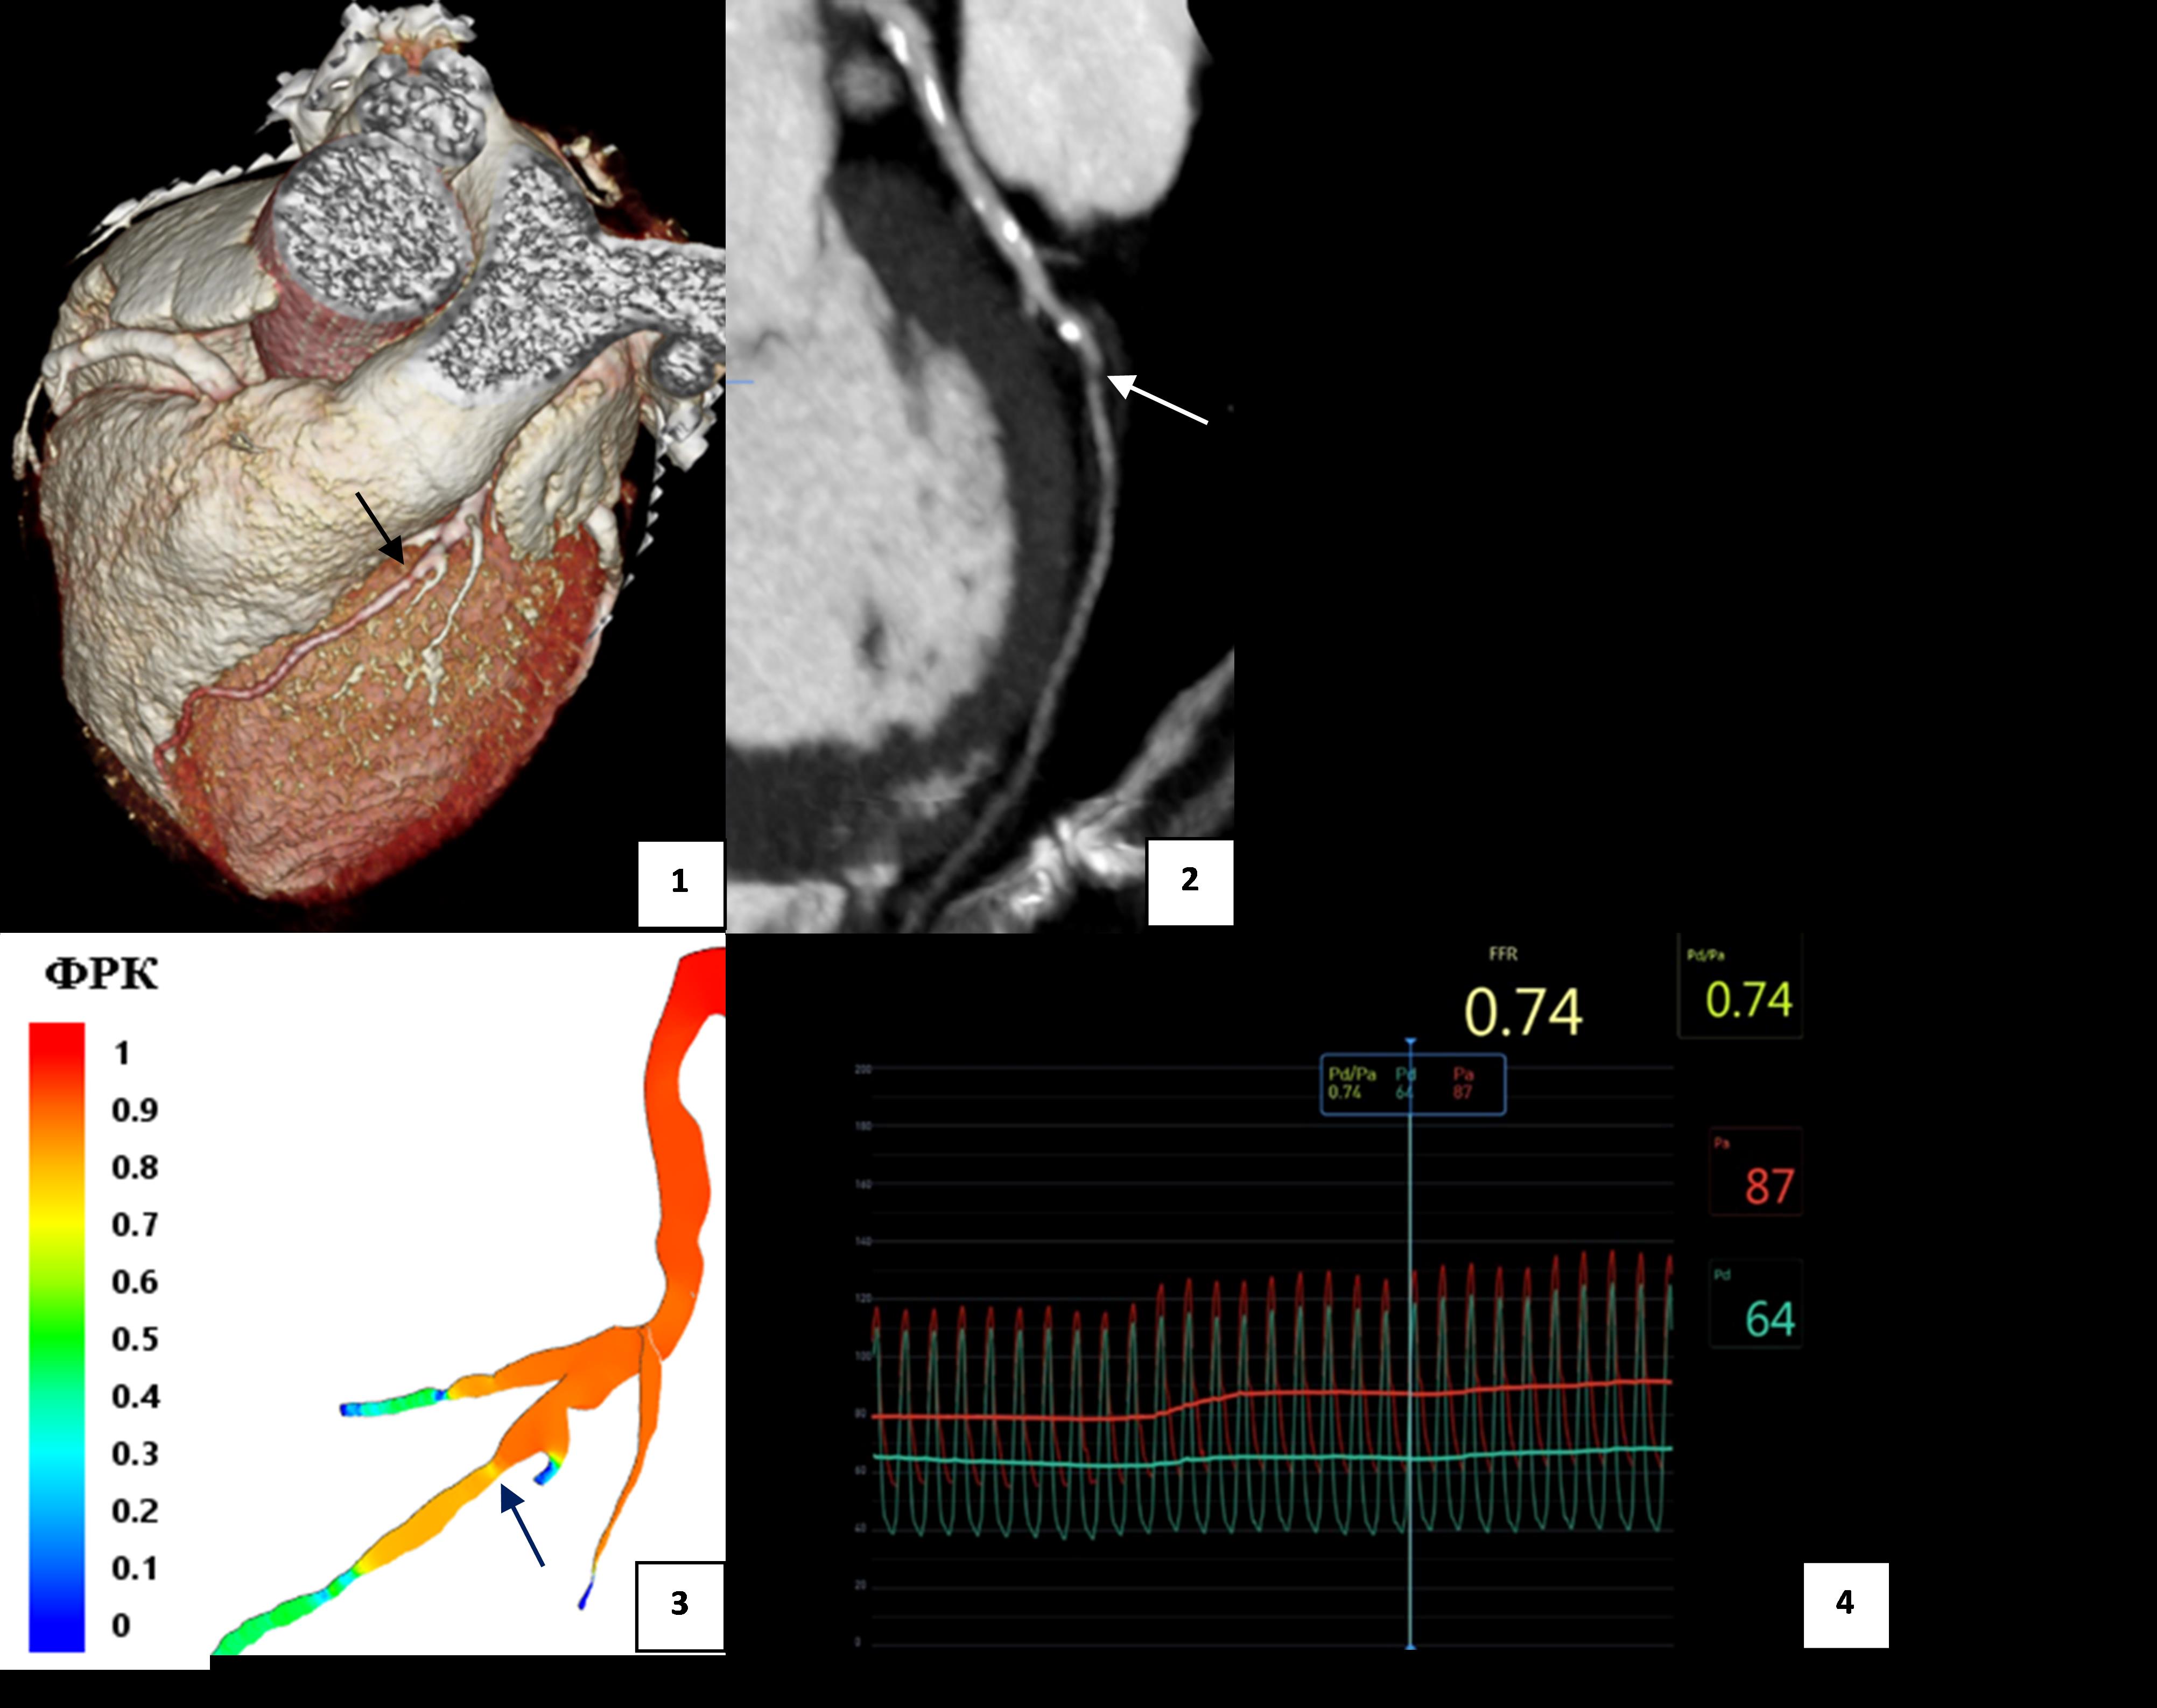

3. Клинический пример (пациент №12): женщина 65 лет с 75% стенозом ПНА. | |